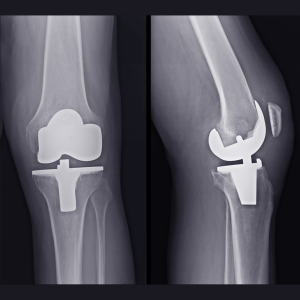

Robotic knee replacement surgery is a type of surgery in which a robot assists the surgeon during the procedure. Contrary to popular belief, the surgery is performed by the surgeon, not the robot. Images obtained through Computed Tomography (CT) and special X-rays are uploaded to the robot before the surgery, allowing for a plan tailored to the patient’s anatomy. The robot used in robotic knee replacement surgery helps ensure that the prosthesis is positioned at the correct angles without errors and supports precise bone cuts. Since the preoperative planning is done by the surgeon, it is important to choose doctors specialized in prosthetic surgery and hospitals with adequate infrastructure for such procedures.

- In robotic knee replacement surgery, two separate metallic implants are placed in the patient’s femur and tibia. These small pins help the robot match the patient’s anatomy with the preloaded images. They also enable the robot to track the patient’s position in space and monitor changes during the surgery.

- There is no need for the guides typically used in traditional knee replacement surgeries when performing robotic knee replacement. The robot calculates and positions the implant with millimetric precision, reducing the margin of error to zero.